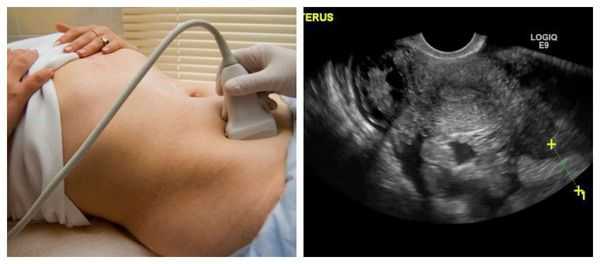

Ультразвуковое исследование органов малого таза является наиболее простым и высокоинформативным методом диагностики различных кист яичников.

При диагностике кист яичников не стоит полагаться только на инструментальные методы исследования, необходимо провести подробный сбор анамнестических данных, жалоб, особенностей менструального цикла пациентки, установление дня цикла, а также проведения теста на беременность в случае задержки, для исключения внематочной локализации плодного яйца. При бимануальном исследовании стоит обратить внимание на наличие, а также подвижность и болезненность патологических образований в проекции яичников.

Безусловно, проведение ультразвуковой диагностики трансабдоминальным и трансвагинальным датчиками позволит не только выявить локализацию кисты, но и определить ее структуру, размеры, характер жидкостного содержимого, определить тактику лечения пациентки. Особенностью фолликулярных кист при ультразвуковом исследовании является тонкостенная капсула с отсутствием сосочков внутренней стороны капсулы. [10] Диагностировать кистозные образования у беременных женщин значительно труднее, ввиду увеличения размеров матки на соответствующих сроках беременности, поэтому ультразвуковое исследование стоит проводить с ЦДК и доплерометрией [11] .